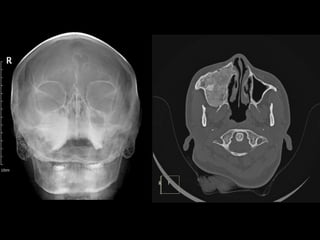

Esthesioneuroblastoma (ENB) • Alsoknown as Olfactory neuroblastomas,. • Rare malignant neuroectodermal tumor arising from olfactory mucosa. • Bimodal distribution - 2nd & 6th decade • Kadish Classification: A - nasal tumor, B - involvement of nasal cavity + sinuses, C - beyond sinuses, D – involvement of cervical lymph nodes.

• 54.

• CT: Cribriformplate destruction, bony remodelling of nasal cavity. •MRI: Intermediate-high signal on T2, dumb-bell shaped, avid enhancement, cysts in intracranial component -Peritumoural cysts between it and the overlying brain are often present, T2*GRE- blooming foci. • Treatment: Craniofacial resection + radiotherapy